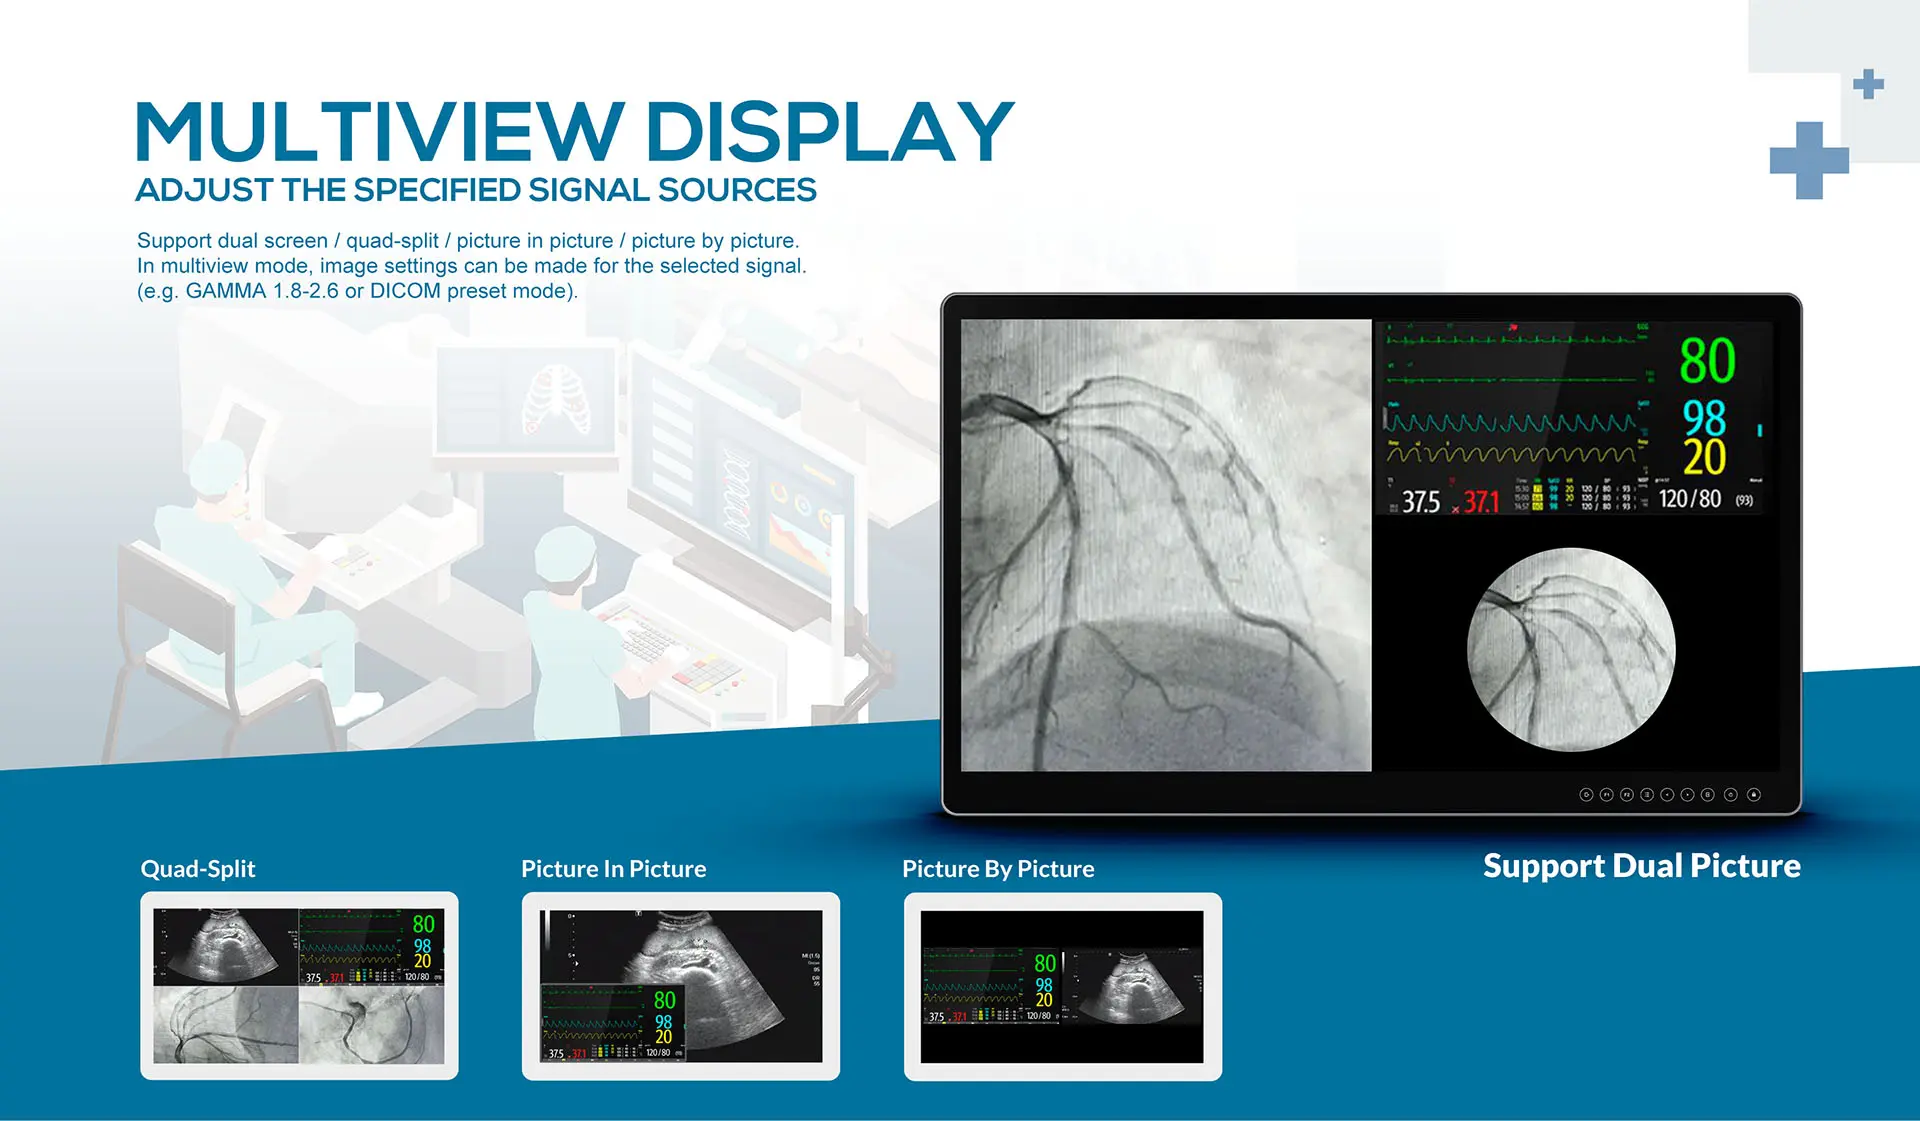

- Multiview display (Dual screen / PlP / PBP / Quad-Split)